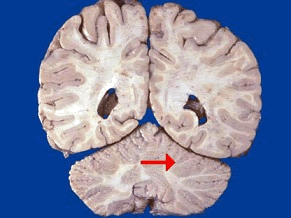

如图箭头所示为大脑哪个部位()<img border="0" style="width: 299px; height: 224px;" src="

[单选题]如图箭头所示为大脑哪个部位()A.壳核B.颞叶C.尾状核D.岛叶E.海马